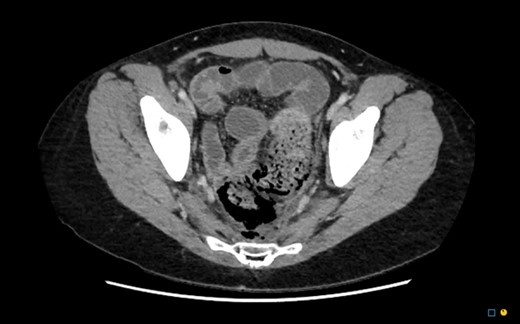

In the regional hospital, the patient had progressive peritonitis and vomiting. He was tachycardic and febrile (Temp 38.5°C). His initial work up demonstrated urea 11.9 mmol/l, creatinine 121 umol/l, C-reactive protein 201 mg/l, white cell count 30.7 × 109/l and haemoglobin 112 g/l. An urgent CT abdomen and pelvis demonstrated a large amount of free gas in the perirectal space consistent with a rectal perforation (Figs 1–3). The rectum itself was thick-walled and oedematous, as well as the sigmoid colon. He was transferred to the referral Tertiary hospital where an urgent laparotomy was performed.

CT axial. Free gas within the pelvis around the rectum as well as pneumointestinalis of the rectum suggestive of ischaemia and perforation.